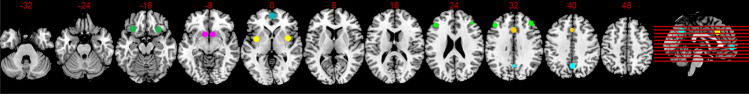

First-level analysis of the rsFC data was performed by using SCA (e.g., Fox et al. 2005; Greicius et al. 2003). A priori atlas regions (CONN default atlas combines FSL Harvard–Oxford atlas for cortical and subcortical areas and AAL atlas for cerebellar parcellation) were defined as seed regions from which the reference time course is formed, and which are correlated with the time courses of all other voxels in the brain. Thus, an FC map was generated for each individual, taking into account both positive and negative correlations. The seeds consisted of spheres with a diameter of 10 mm and are already implemented in the CONN toolbox (Whitfield-Gabrieli and Nieto-Castanon 2012). Since most intrinsic networks are lateralized (Agcaoglu et al. 2015), each hemisphere was examined separately (with the exception of midline structures). A schematic representation of the examined seeds and their coordinates is shown in Fig. 2.

Fig. 2.

Schematic display of examined neural systems with corresponding nodes. Impulsive System (violet): Nucleus accumbens left (− 9.5, 12, − 7), Nucleus accumbens right (9, 12, − 7); Reflective System (green): lateral prefrontal cortex left (− 43, 33, 28), lateral prefrontal cortex right (41, 38 30), orbitofrontal cortex left (− 30, 24, − 17), orbitofrontal cortex right (29, 23, − 16); Salience Network (yellow): anterior cingulate Cortex (0, 22, 35), insular cortex left (− 36, 1, 0), insular cortex right (37, 3, 0): Default Mode Network (blue): medial prefrontal cortex (1, 55, − 3); posterior cingulate cortex (1, − 61, 38)